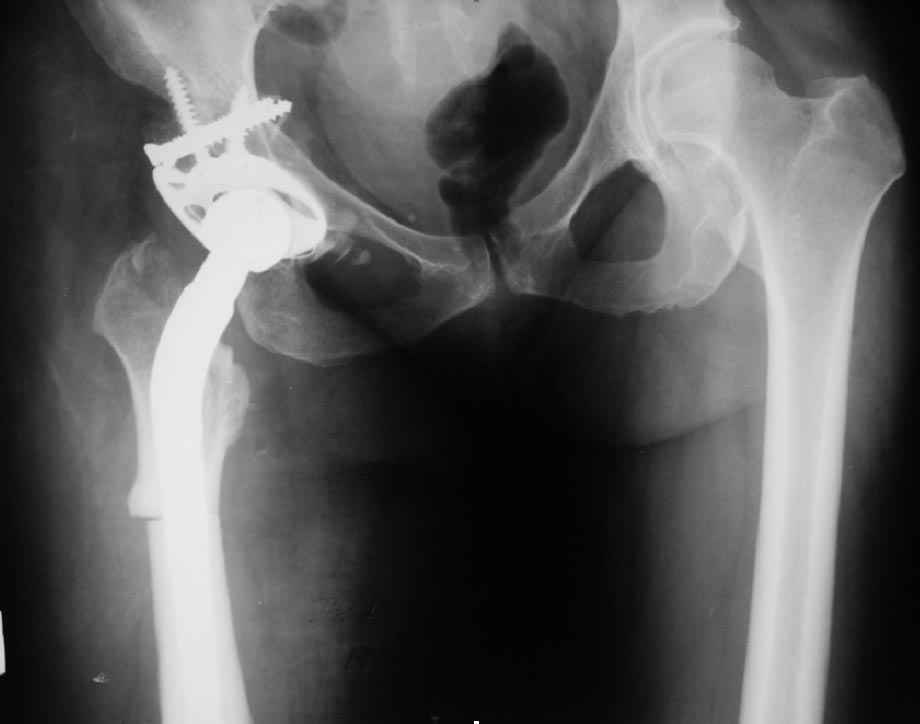

Был у нас подобный случай

Выполнена одномоментная коррекция деформации, эндопротезирование DePyu Pinnacle-AML. Пластинка с деротационной целью. При использовании ножки с прямоугольным сечением, думаю, можно и без нее.

В прищепке случай 1999 года - эндопротезирование после операции Шанца-Илизарова. Возраст пациентки 45. Коррекция была в 17 лет. А Рыков Хабаровск.